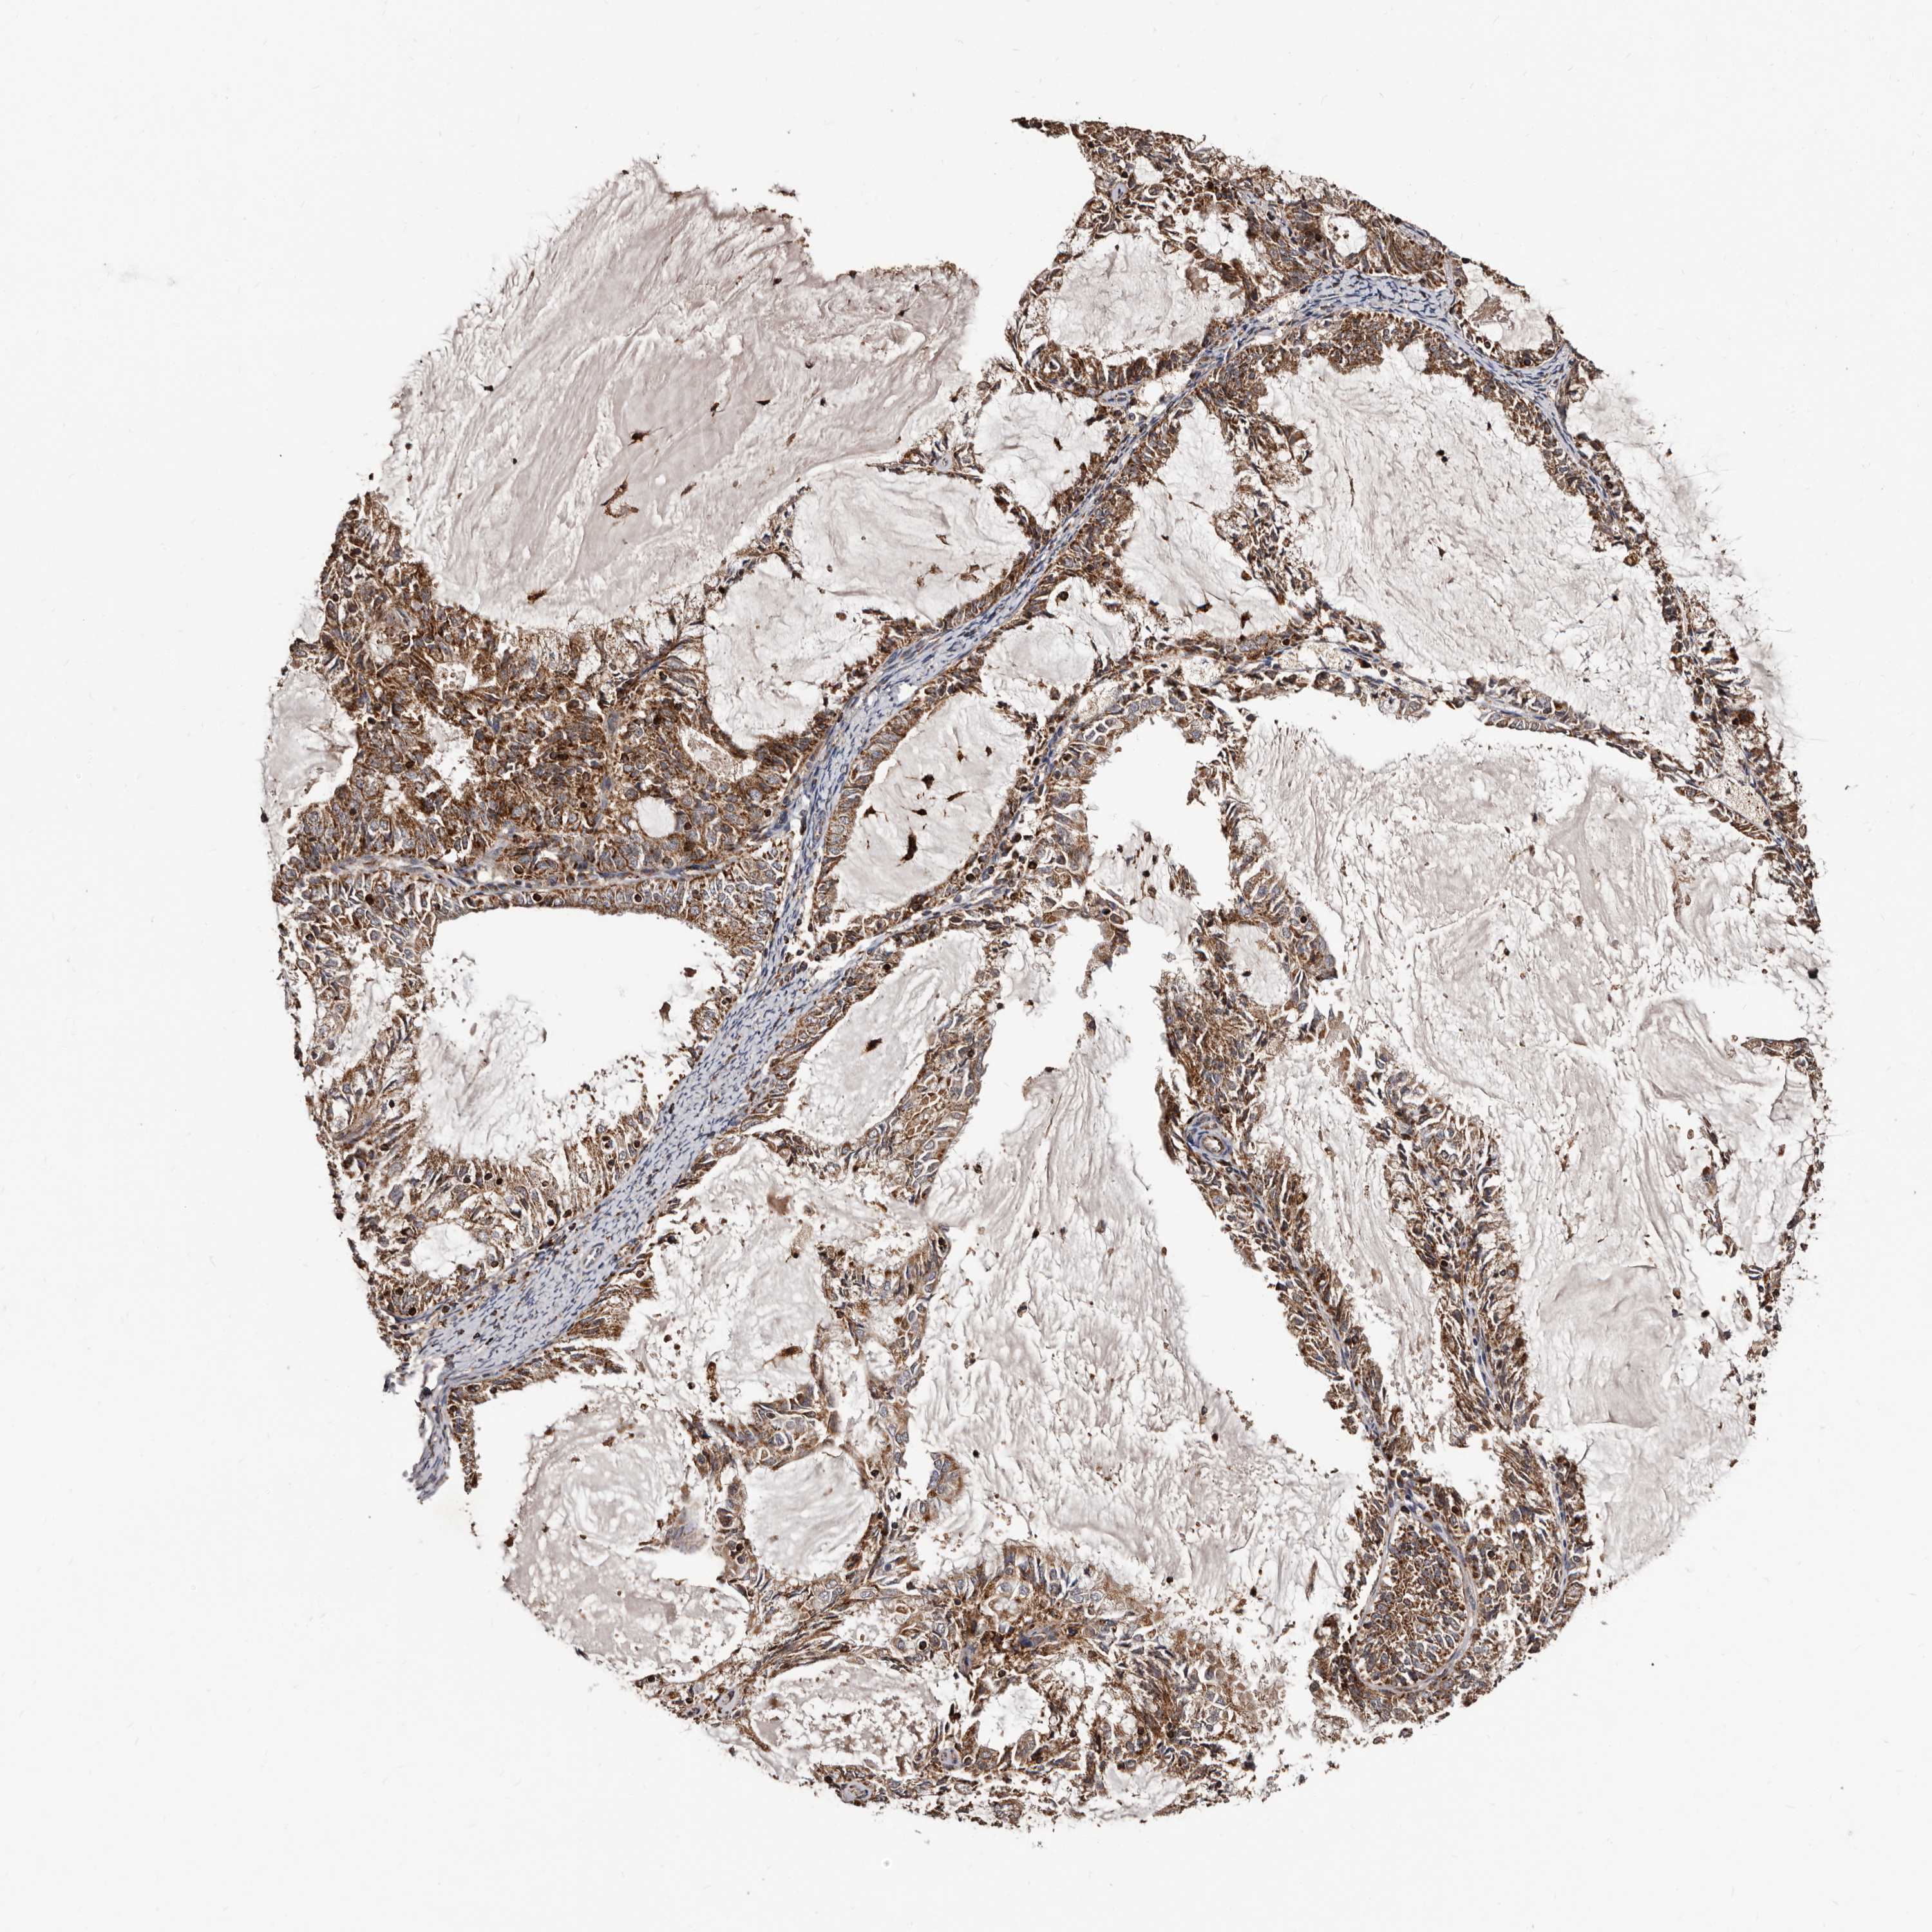

ENDOMETRIAL CANCER - Protein expressioni

A mouse-over function shows sample information and annotation data. Click on an image to view it in a full screen mode. Samples can be filtered based on level of antibody staining by selecting one or several of the following categories: high, medium, low and not detected. The assay and annotation is described here.

Note that samples used for immunohistochemistry by the Human Protein Atlas do not correspond to samples in the TCGA dataset.

Antibody stainingi

Antibody staining in the annotated cell types in the current human tissue is reported as not detected, low, medium, or high, based on conventional immunohistochemistry profiling in selected tissues. This score is based on the combination of the staining intensity and fraction of stained cells.

Each image is clickable and will lead to virtual microscopy that enables deeper exploration of all samples and also displays staining intensity scores, fraction scores and subcellular localization as well as patient and tissue information for each sample.

Antibody HPA027878

Antibody CAB004206

Staining

High

Medium

Low

Not detected

Intensity

Strong

Moderate

Weak

Negative

Quantity

>75%

75%-25%

<25%

None

Location

Nuclear

Cytoplasmic/membranous

Cytoplasmic/membranous,nuclear

Adenocarcinoma, NOS